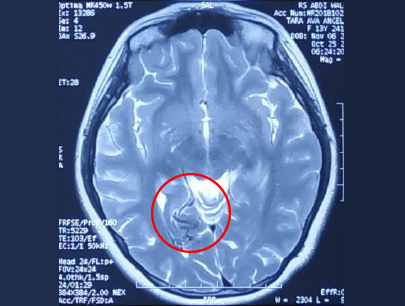

AVM (Arterivenous Malformation)

Kelainan pembuluh darah otak non-stroke

SEBELUM

SESUDAH

(Perempuan, 14 tahun)

Diagnosis: Malformasi Arteri-Vena Oksipital Kanan

Sebelum Gamma Knife

• Nyeri Kepala

3 bulan Setelah Gamma Knife

• Kebutaan menetap

• Penonjolan mata kiri berkurang

Diameter Nidus: 1.5 cm

Nidus tidak ada